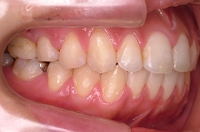

CASE1

前歯の歯並びが悪いのが一番気になります。

右側では良く噛めません↓(16歳/女性)

概要・担当医コメント:叢生・右側咀嚼障害↑

マルチブラケット装置/動的治療期間26ヶ月(23回)

/費用概算:60万円

高校の部活も矯正も両方頑張れたそうです。

上顎右側の小臼歯を1本のみ抜歯させていただき,あとは上下の歯列アーチ形態の修正にて矯正できました。